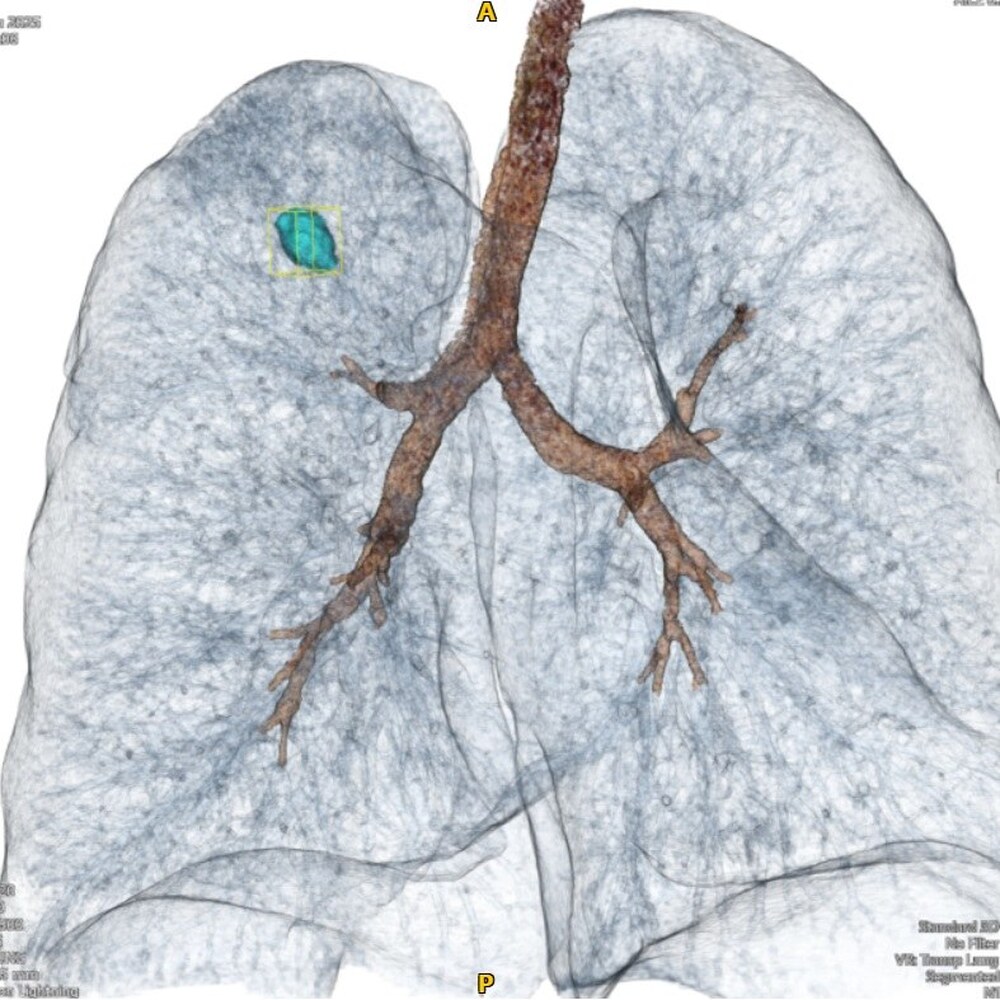

Екипите са осъществили биопсия на белодробен възел, т.нар. нодул, с размери едва 14 мм, разположен дълбоко в белодробната тъкан. Интервенцията изисква максимална прецизност и перфектна координация, каза Кръстева.

Тя уточни, че пациентът, който е имал онкологична история, е подложен на процедурата с цел да се установи дали „нодулът“ представлява метастаза или вторичен първичен тумор. За да се преодолеят предизвикателствата на този сложен случай, е поканен д-р Пейчев, който е работил в тясно сътрудничество с началника на отделението по хирургия д-р Симеон Симеонов, началника на отделението по образна диагностика д-р Ивелин Васков и хирурга д-р Кольо Карахристов.

Стела Кръстева добави, че процедурата, извършена под контрола на компютърна томография, е преминала успешно и без усложнения, а пациентът е изписан само три дни по-късно.